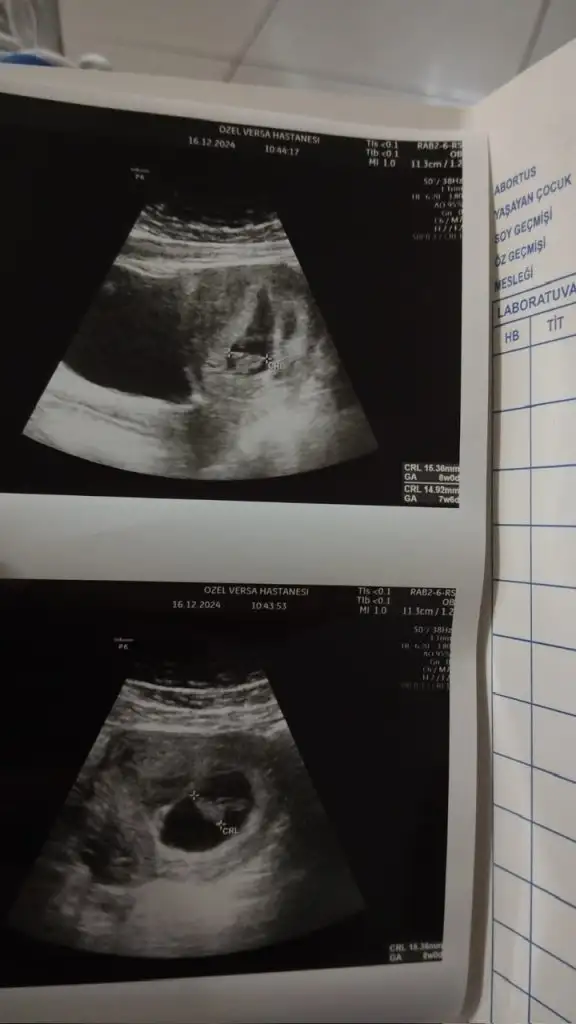

Üsteki kız alttaki erkek gibime geliyor sizceKızlar ikiz bebişler bence bir kız bi erkeksizce

Karından ise üstteki erkek alttaki kız benceKızlar ikiz bebişler bence bir kız bi erkeksizce

Burda 8+5gunluk .. inşallah hayırlısı kalp atışında duyarsiniz kucaginizada alırsınız birde erkek olduğunu nerden anladinzSizinde erkek sanırımkaç haftalık bende haftaya cuma gidicem kalp atışı için bugün 6+2 benim keseye de gitmedim hiç bakalım benim ultrason kağıdı nasıl